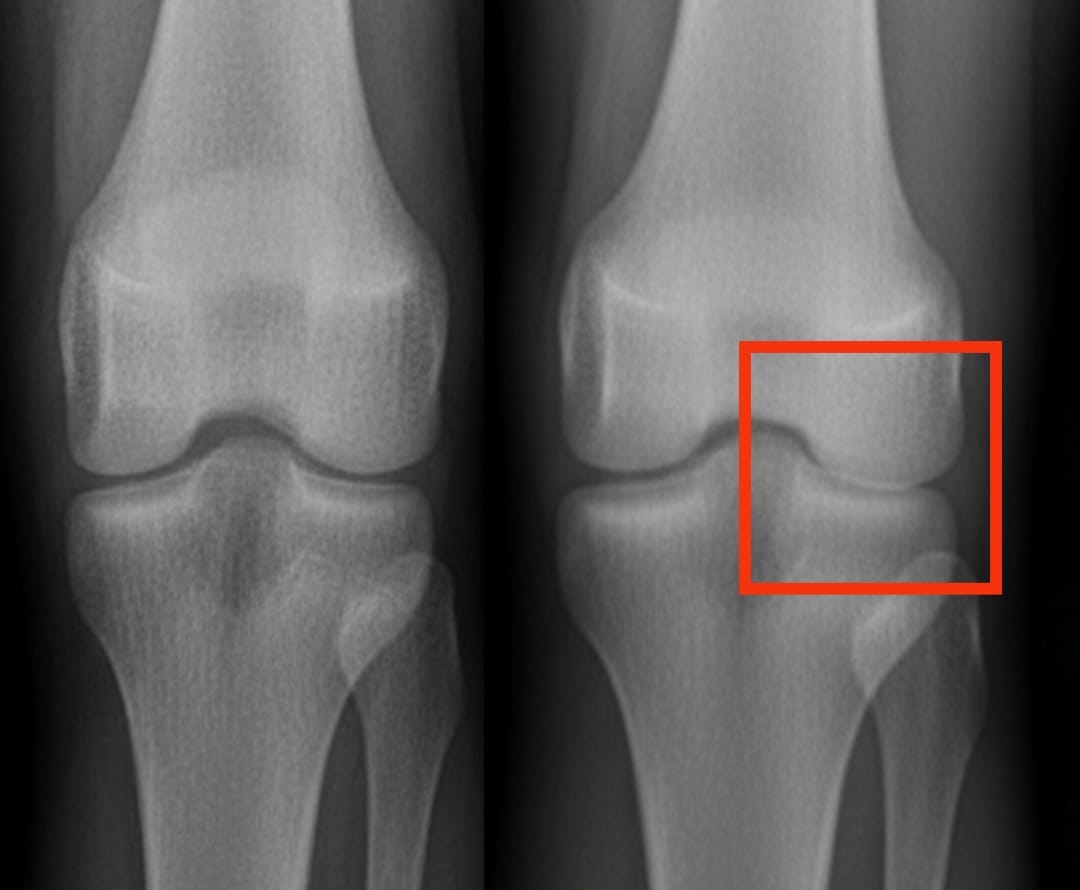

Knee osteoarthritis affects hundreds of millions of people worldwide. It is characterized by the progressive wear of cartilage, leading to pain and difficulty moving. Among the proposed solutions, platelet-rich plasma injections are generating increasing interest. This treatment uses the patient’s own blood, concentrated in platelets, to stimulate tissue repair and reduce inflammation.